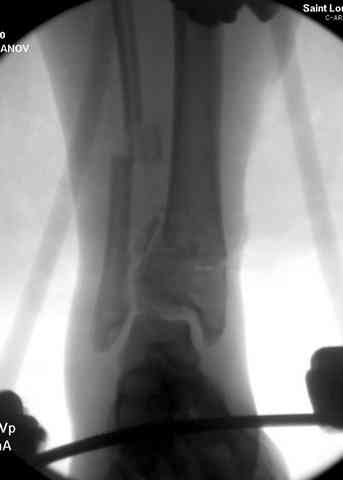

Яков изложил все необходимые аспекты лечения переломов пилона, и, не желая менять тему, решил выставить нашу точку зрения в двух клинических примерах.

При лечении внутрисуставных переломов типа "Pilon"

или "Tibial Plateau" на голени, применение простых

наружных фиксаторов типа "Spanning ExFix" или "Travelling ExFix" стал одним из стандартом этапного лечения.

В первые часы после поступления больным экстренно накладывается простой фиксатор из двух поперечно проведенных стержней или сооружается "Delta

Frame" в зависимости от места локализации, и проводится дистракция.

Здесь выставлена пара случаев перелома пилона, оба

случая леченные этапным наружным фиксатором.